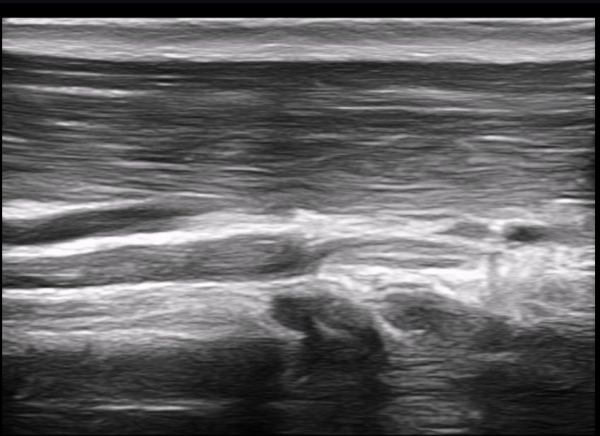

±ÙÀ°ÇǺνŰæÀÇ Á¾´Ü¸é°Ë»ç¿¡¼­ ±ÙÀ°ÇǺνŰæÀÇ ±¹¼ÒÀû ÇùÂø°ú ±ÙÀ§ºÎÀÇ Àú¿¡ÄÚ ºÎÁ¾ÀÌ °üÂûµÈ´Ù

(»çÁø 4, 5, 6,7) À̰ÍÀº ½Å°æÀÇ ¿°Àü(torsion)¿¡ ºÎÇÕÇÏ´Â ¼Ò°ßÀÌ´Ù.

½Å°æ º´º¯ÀÇ ÇǺο¡ Ç¥½Ã ÷ºÎÆÄÀÏ 5